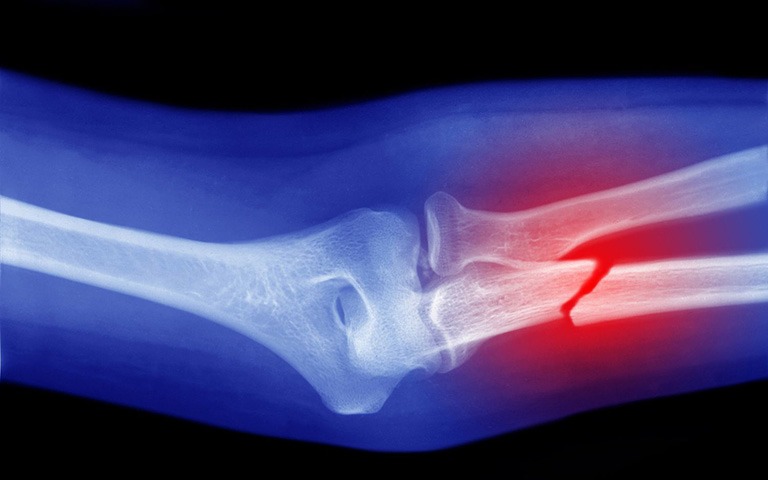

Gãy xương là tình trạng mà cấu trúc xương bị nứt hoặc vỡ do tác động từ nhiều nguyên nhân khác nhau. Lực tác động có thể là trực tiếp hoặc gián tiếp:

Gãy xương được phân loại thành hai loại chính là gãy xương kín và gãy xương hở, đôi khi có một loại đặc biệt được gọi là gãy xương biến chứng.

Thông thường, việc nhận biết loại gãy xương và mức độ nghiêm trọng của nó đóng vai trò quan trọng trong việc xác định phương pháp điều trị và sơ cứu hiệu quả.